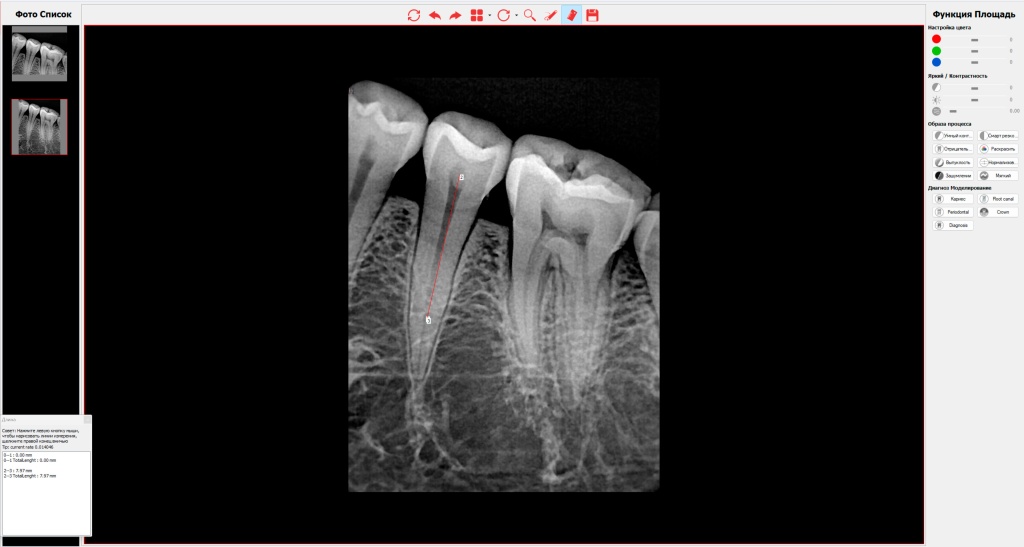

- •Калибровка и замеры: Инструмент точного линейного измерения позволяет оценивать рабочую длину корневого канала, глубину кариозной полости или диаметр периапикальной кисты.

- •Детализация: Цифровая лупа предназначена для многократного увеличения сложных участков (например, апекса или бифуркации корней).